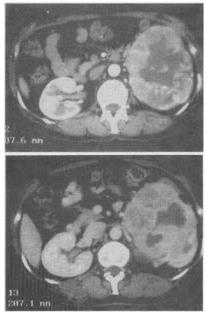

- 单项选择题 患者,女,58岁。左腰部不适,血尿2个月余。CT检查见图。最有可能的诊断是()。

A、肾癌

B、肾盂癌

C、肾错构瘤

D、肾囊肿

E、肾脓肿

- A